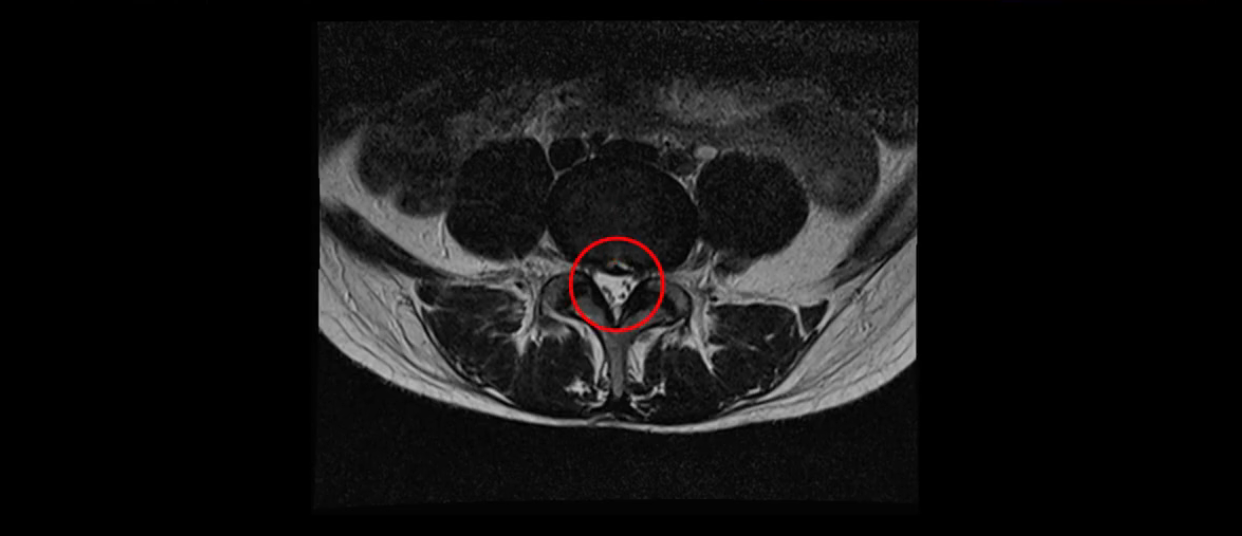

이분 MRI를 보시면 두 마디의 퇴행성디스크가 있습니다. 그리고 디스크가 조금씩 밀려 나와 있고요. 그런데 디스크 탈출 정도는 두 마디 다 심하지 않습니다. 4번 5번에는 디스크 탈출이 약간 있고,

또한 양쪽 신경 가지가 빠져나가는 추간공은 매우 넓은 상태입니다.

중요한 것은 이 정도 경미한 탈출과 협착으로는 양쪽 다리가 저리고 아플 수가 없습니다.

그리고 만약에 이 디스크가 급성으로 찢어진 것이라면 아주 심한 디스크성 통증이 있겠죠. 기침이나 재채기를 하면 심하게 아프고 허리를 조금만 구부려도 아주 날카로운 통증들이 생길 겁니다. 그런데 이분은 이런 증상이 전혀 아닙니다. 디스크의 돌출 정도와 협착이 전혀 심하지 않기 때문에 이분이 가지고 계신 양쪽 다리 저림, 특히 이분은 누워있을 때도 양쪽 다리가 저리다고 하는데, 디스크 때문에 그런 증상은 생길 수가 없습니다. 또 이 디스크는 오래된 디스크, 이미 찢어진 섬유륜이 아문 디스크이고, 그러니까 이분은 기침이나 재채기를 못하는 증상이 없는 거죠. 그 다음에 허리를 구부릴 때 뻐근한 증상은 있지만 아주 날카로운 통증은 없습니다.

이분 MRI를 보시면 퇴행성디스크가 있고 약간의 협착이 있지만 이 정도의 퇴행성디스크와 협착으로는 신경이 눌려서 양쪽 다리가 저리고 아픈 증상이 나올 수가 없습니다. 그래서 MRI와 이 환자분의 다리 증상이 매치가 안 된다고 하는 의사들이 많은 겁니다.